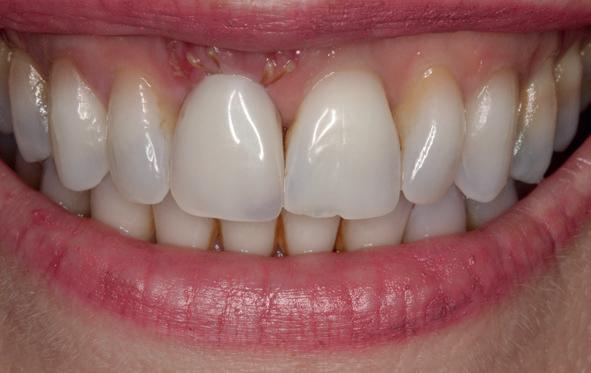

Implantologische behandelingen in het esthetische front vragen meer dan technische vaardigheid alleen. Ze vragen om overzicht, timing, vertrouwen en een team dat als vanzelf samenwerkt onder druk. Juist bij complexe casussen, waarin angst, infectie en hoge esthetische verwachtingen samenkomen, wordt zichtbaar hoe bepalend de rol van de tandartsassistent is.

Deze casus beschrijft een uitgebreide immediate implantaatbehandeling bij een patiënt die door meerdere collega’s werd geweigerd. Niet omdat de mogelijkheden ontbraken, maar omdat de complexiteit vroeg om een perfect afgestemde samenwerking. Het verhaal laat zien hoe de assistent in zo’n traject veel meer is dan een uitvoerende kracht of “mal”, maar een dynamische surgical guide die het proces mede stuurt, bewaakt en mogelijk maakt.De patiënt: wanneer alles samenkomt

In de prothetische fase (zie foto’s) is in de bovenkaak gebruikgemaakt van verschroefde zirconia bruggen, die enkel buccaal zijn opgebakken. Deze bruggen zijn verlijmd op individuele, geanguleerde titanium abutments. In de onderkaak is een verschroefde kunststofbrug op een titaniumbasis (wrap-around) gemaakt. Voor deze combinatie is gekozen vanwege een minder hinderlijk tikkend geluid bij functie en kleinere kans op breuk van de keramiek. Een nadeel is verhoogde slijtage van de kunststof elementen, maar deze zijn in de jaren later eenvoudig te vervangen op de bestaande brug. Ondanks alle digitale mogelijkheden is de afdruk en registratiefase analoog uitgevoerd, omdat in ervaring van de behandelaren dit bij deze totale rehabilitaties op implantaten nog altijd de grootste precisie oplevert. Er is afgedrukt met impregum in individuele lepels en de pasvorm is gecontroleerd met rigide duralay bars. De relatie wordt vastgelegd zoals bij een volledige prothese met waswallen en pijlpuntregistratie. De opstelling in was wordt gepast en laatste correcties worden gemaakt in samenspraak met de patiënt, de restauratieve tandarts en de tandtechnicus. Na het vastzetten van de suprastructuren worden de schroefgaten afgesloten met composiet.

Patiënt G. is van ver gekomen. Voor het behandelplan was interdisciplinair overleg en samenwerking essentieel om tot het gewenste resultaat te kunnen komen. De Kliniek voor Parodontologie Amsterdam (KVPA) - met ruim 40 jaar ervaring op het gebied van implantologie, restauratieve tandheelkunde, parodontologie, endodontologie en gnathologie - is hiervoor de uitgelezen kliniek. En waar het uiteindelijk om draait: de patiënt is tevreden met het behaalde resultaat!